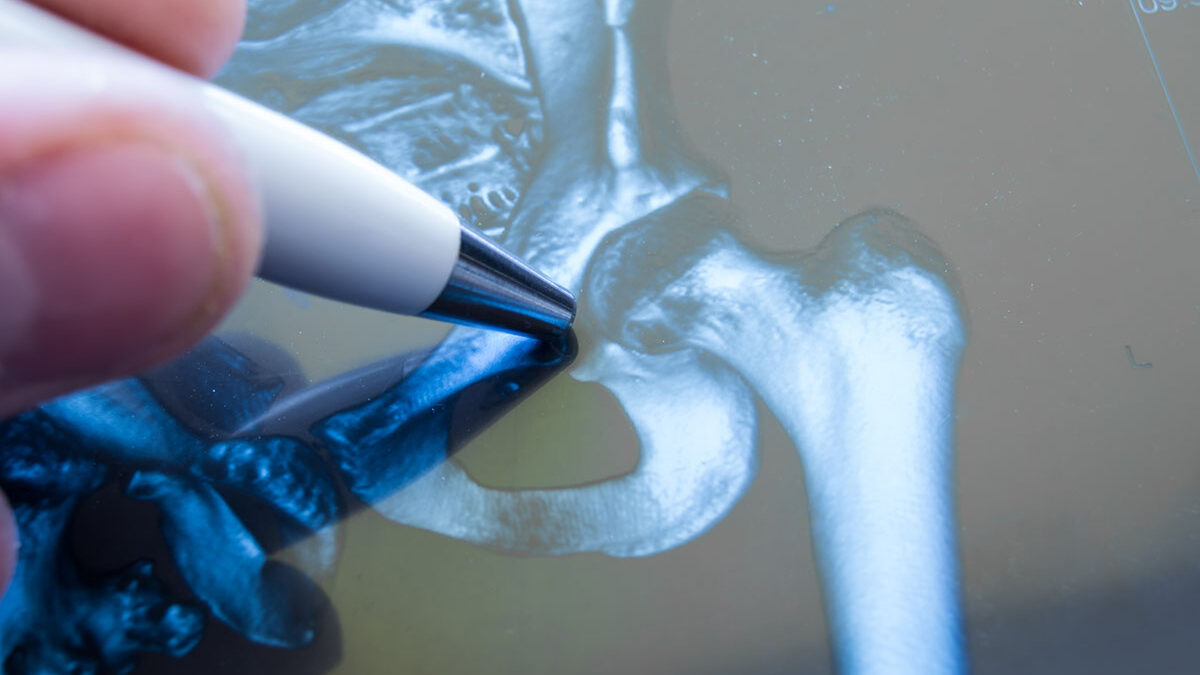

- Hip- For a hip osteotomy, the doctor will reshape your hip socket allowing better coverage of the ball of your hip joint.